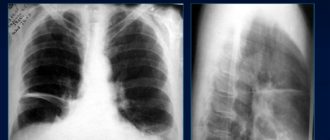

Ателектаз легкого и его долей: виды болезни, симптомы, лечение, рентген-снимки Ателектаз – это патология,